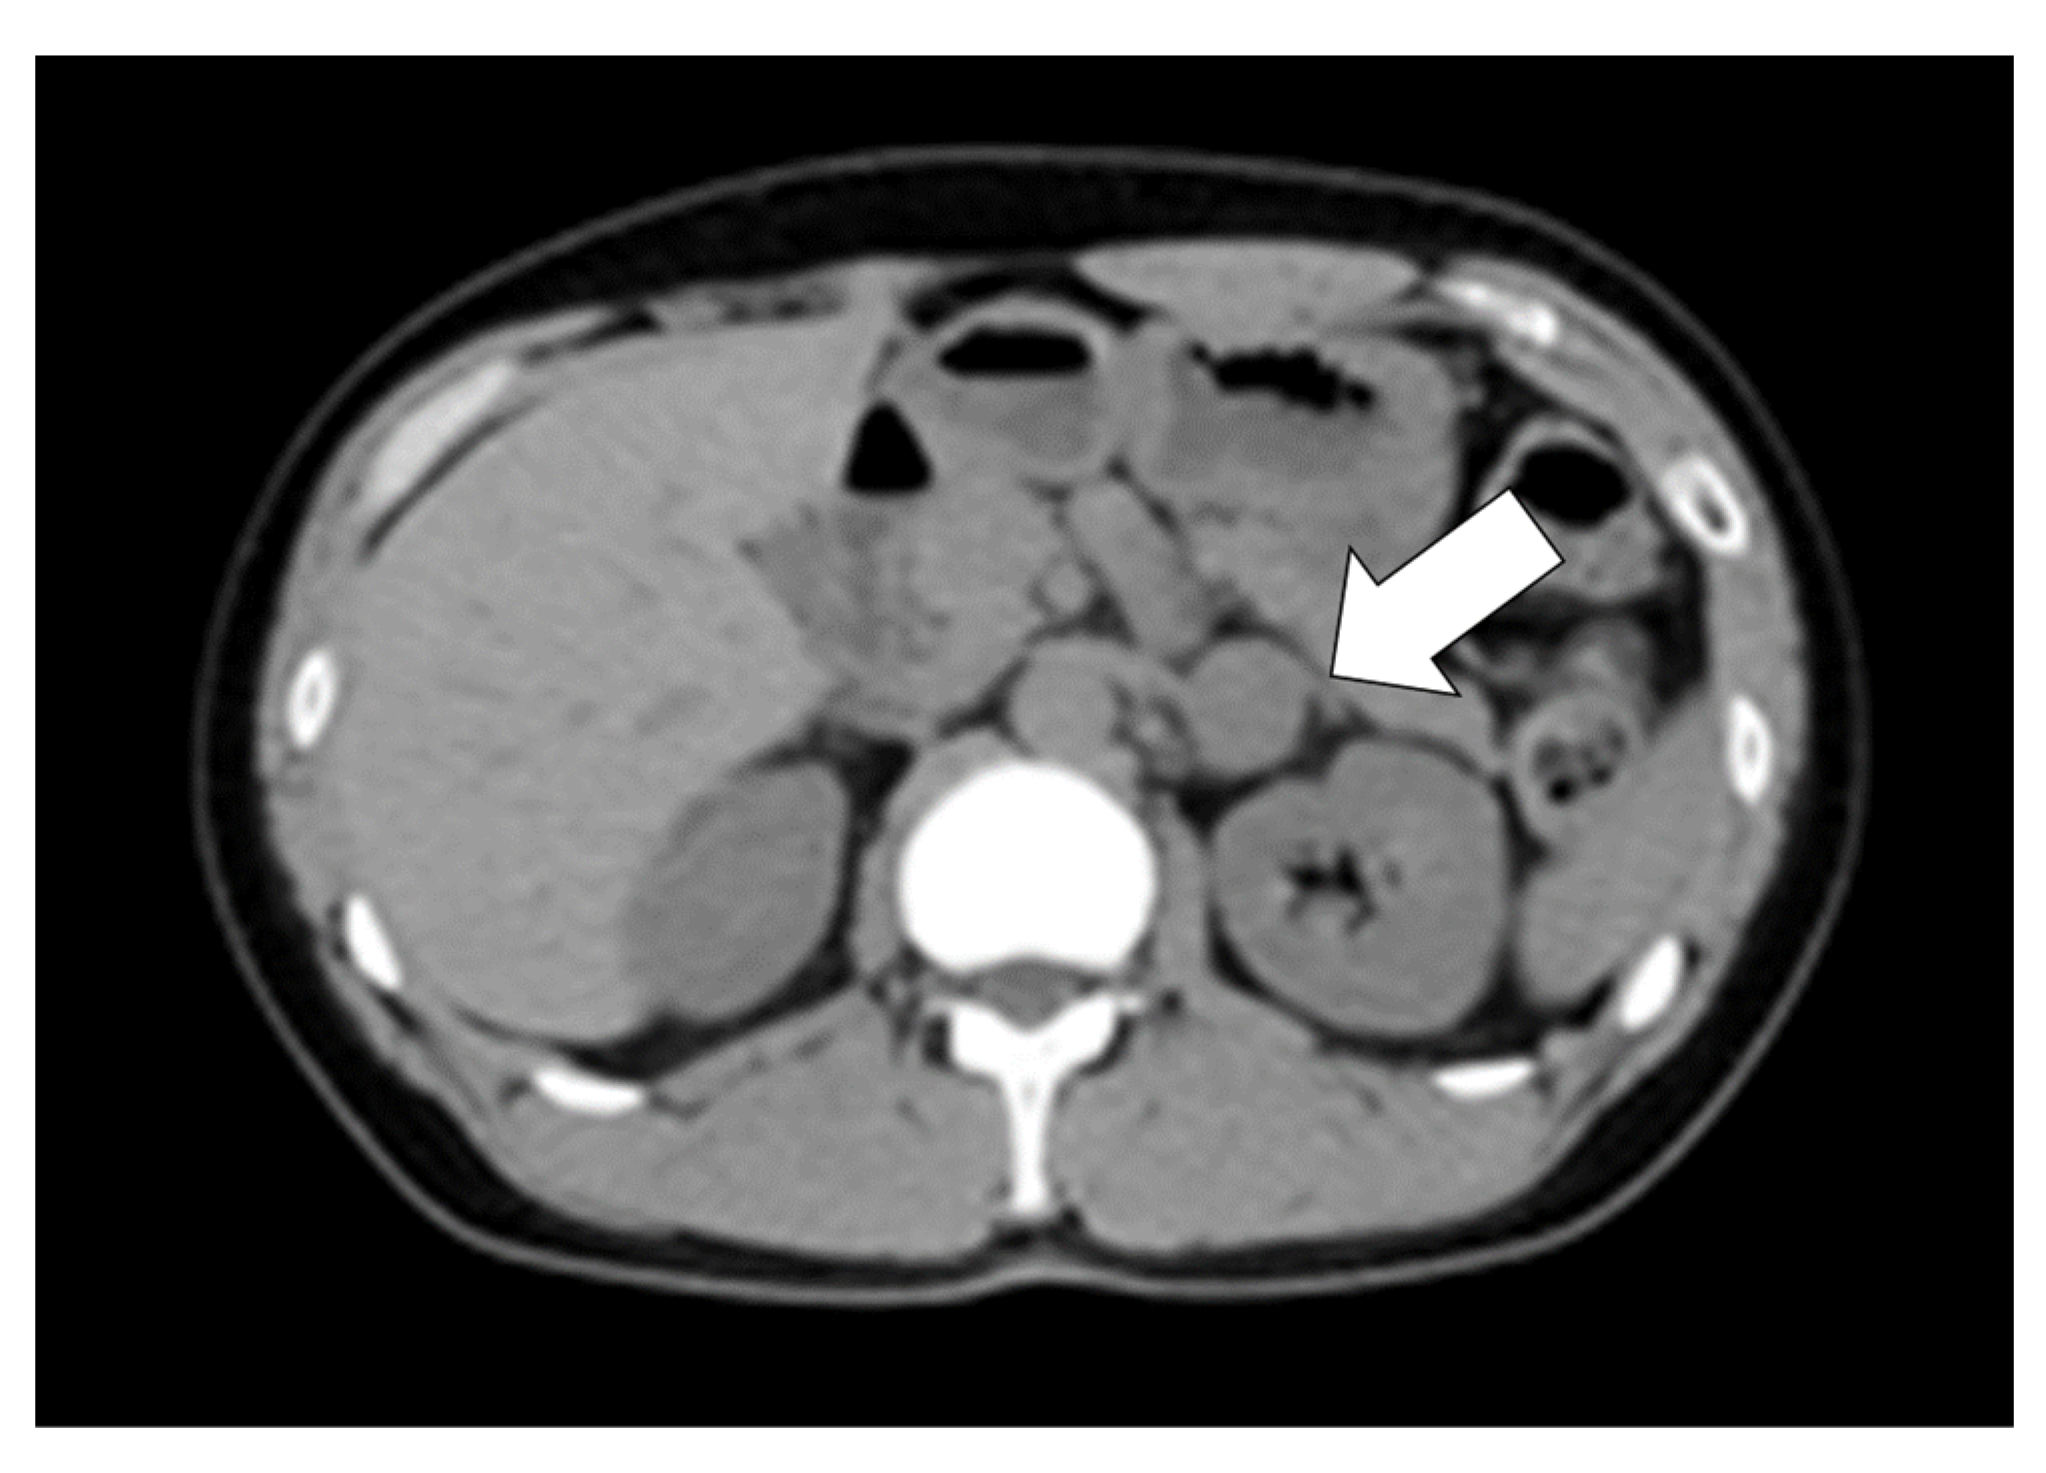

2. Case Presentation